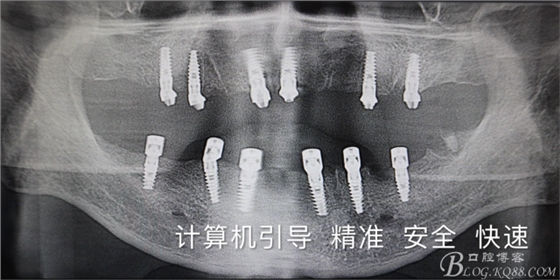

四塊導板.全口種植.即刻負重